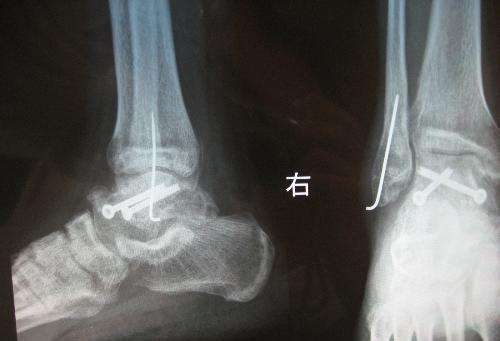

专家提醒骨折的朋友,为了更快恢复健康,最好应该逐渐加强患肢的功能锻炼,同时适当加强营养。患者三个月后再复查,如果X线片提示还不痊愈,可能要再次手术。